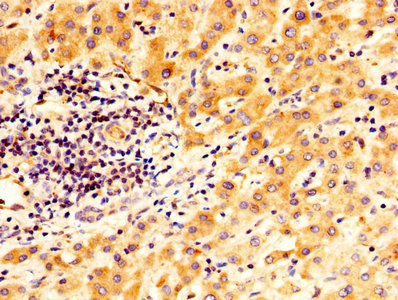

IHC image of CSB-PA11809A0Rb diluted at 1:400 and staining in paraffin-embedded human liver cancer performed on a Leica BondTM system. After dewaxing and hydration, antigen retrieval was mediated by high pressure in a citrate buffer (pH 6.0). Section was blocked with 10% normal goat serum 30min at RT. Then primary antibody (1% BSA) was incubated at 4°C overnight. The primary is detected by a biotinylated secondary antibody and visualized using an HRP conjugated SP system.